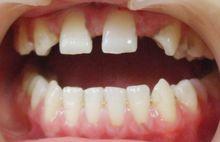

口腔中最突出的表現是先天缺牙,乳牙和恆牙常常全部缺失,或僅有寥寥無幾的牙齒,餘留牙間隙增寬,距離稀疏,牙形小,呈圓錐狀。無牙的部位無牙槽嵴,但頜骨發育不受影響。有的涎腺發育不良,唾液少,口乾。家長常因患兒不長牙而就診諮詢。

有汗型外胚葉發育不全又稱毛髮-指甲-牙齒綜合徵(trichoarycho-dental-syndrome),主要表現是患兒汗腺發育正常,其他表現與無汗型外胚發育不全相似,例如毛髮和眉毛纖細、色淺、稀疏,指甲發育遲緩,菲薄脆弱,有條紋而尤光澤,常可出現甲溝感染而使指(趾)甲基質崩解,或指甲缺失或變厚。口腔表現亦為牙齒先天缺失,缺失牙數不等,或形態發育異常,前牙多呈錐形牙,或釉質發育不良,釉質薄,橫紋明顯或出現小陷窩。